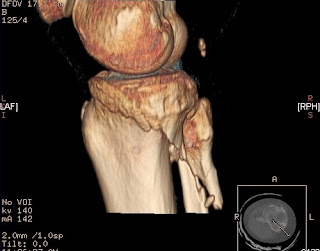

The image results of the CT is what amazed me the most of the entire tour. I was mesmerized by all the planes and angle views we could observe of one specific part of the body. One of the Technologists showed me a knee image and made the image flip around 180 degrees. Then he showed me how he could have the image remove the femur and angle the view from above the tibia and fibula as though we were in the place of the femur. This totally flipped me out! Although there are programs for architecture and animation that allow 3D renderings of something imagined the difference with a CT is that the image is from inside the actual body.

The rotations and unique points of views allow the Technologists to see injuries with very precise information not possible in the past without operating or opening the body (and even then the other tissues and blood could easily get in the way). I pondered this wonder all weekend and kept reviewing the image in my mind. I liken this view of the knees to seed pods.